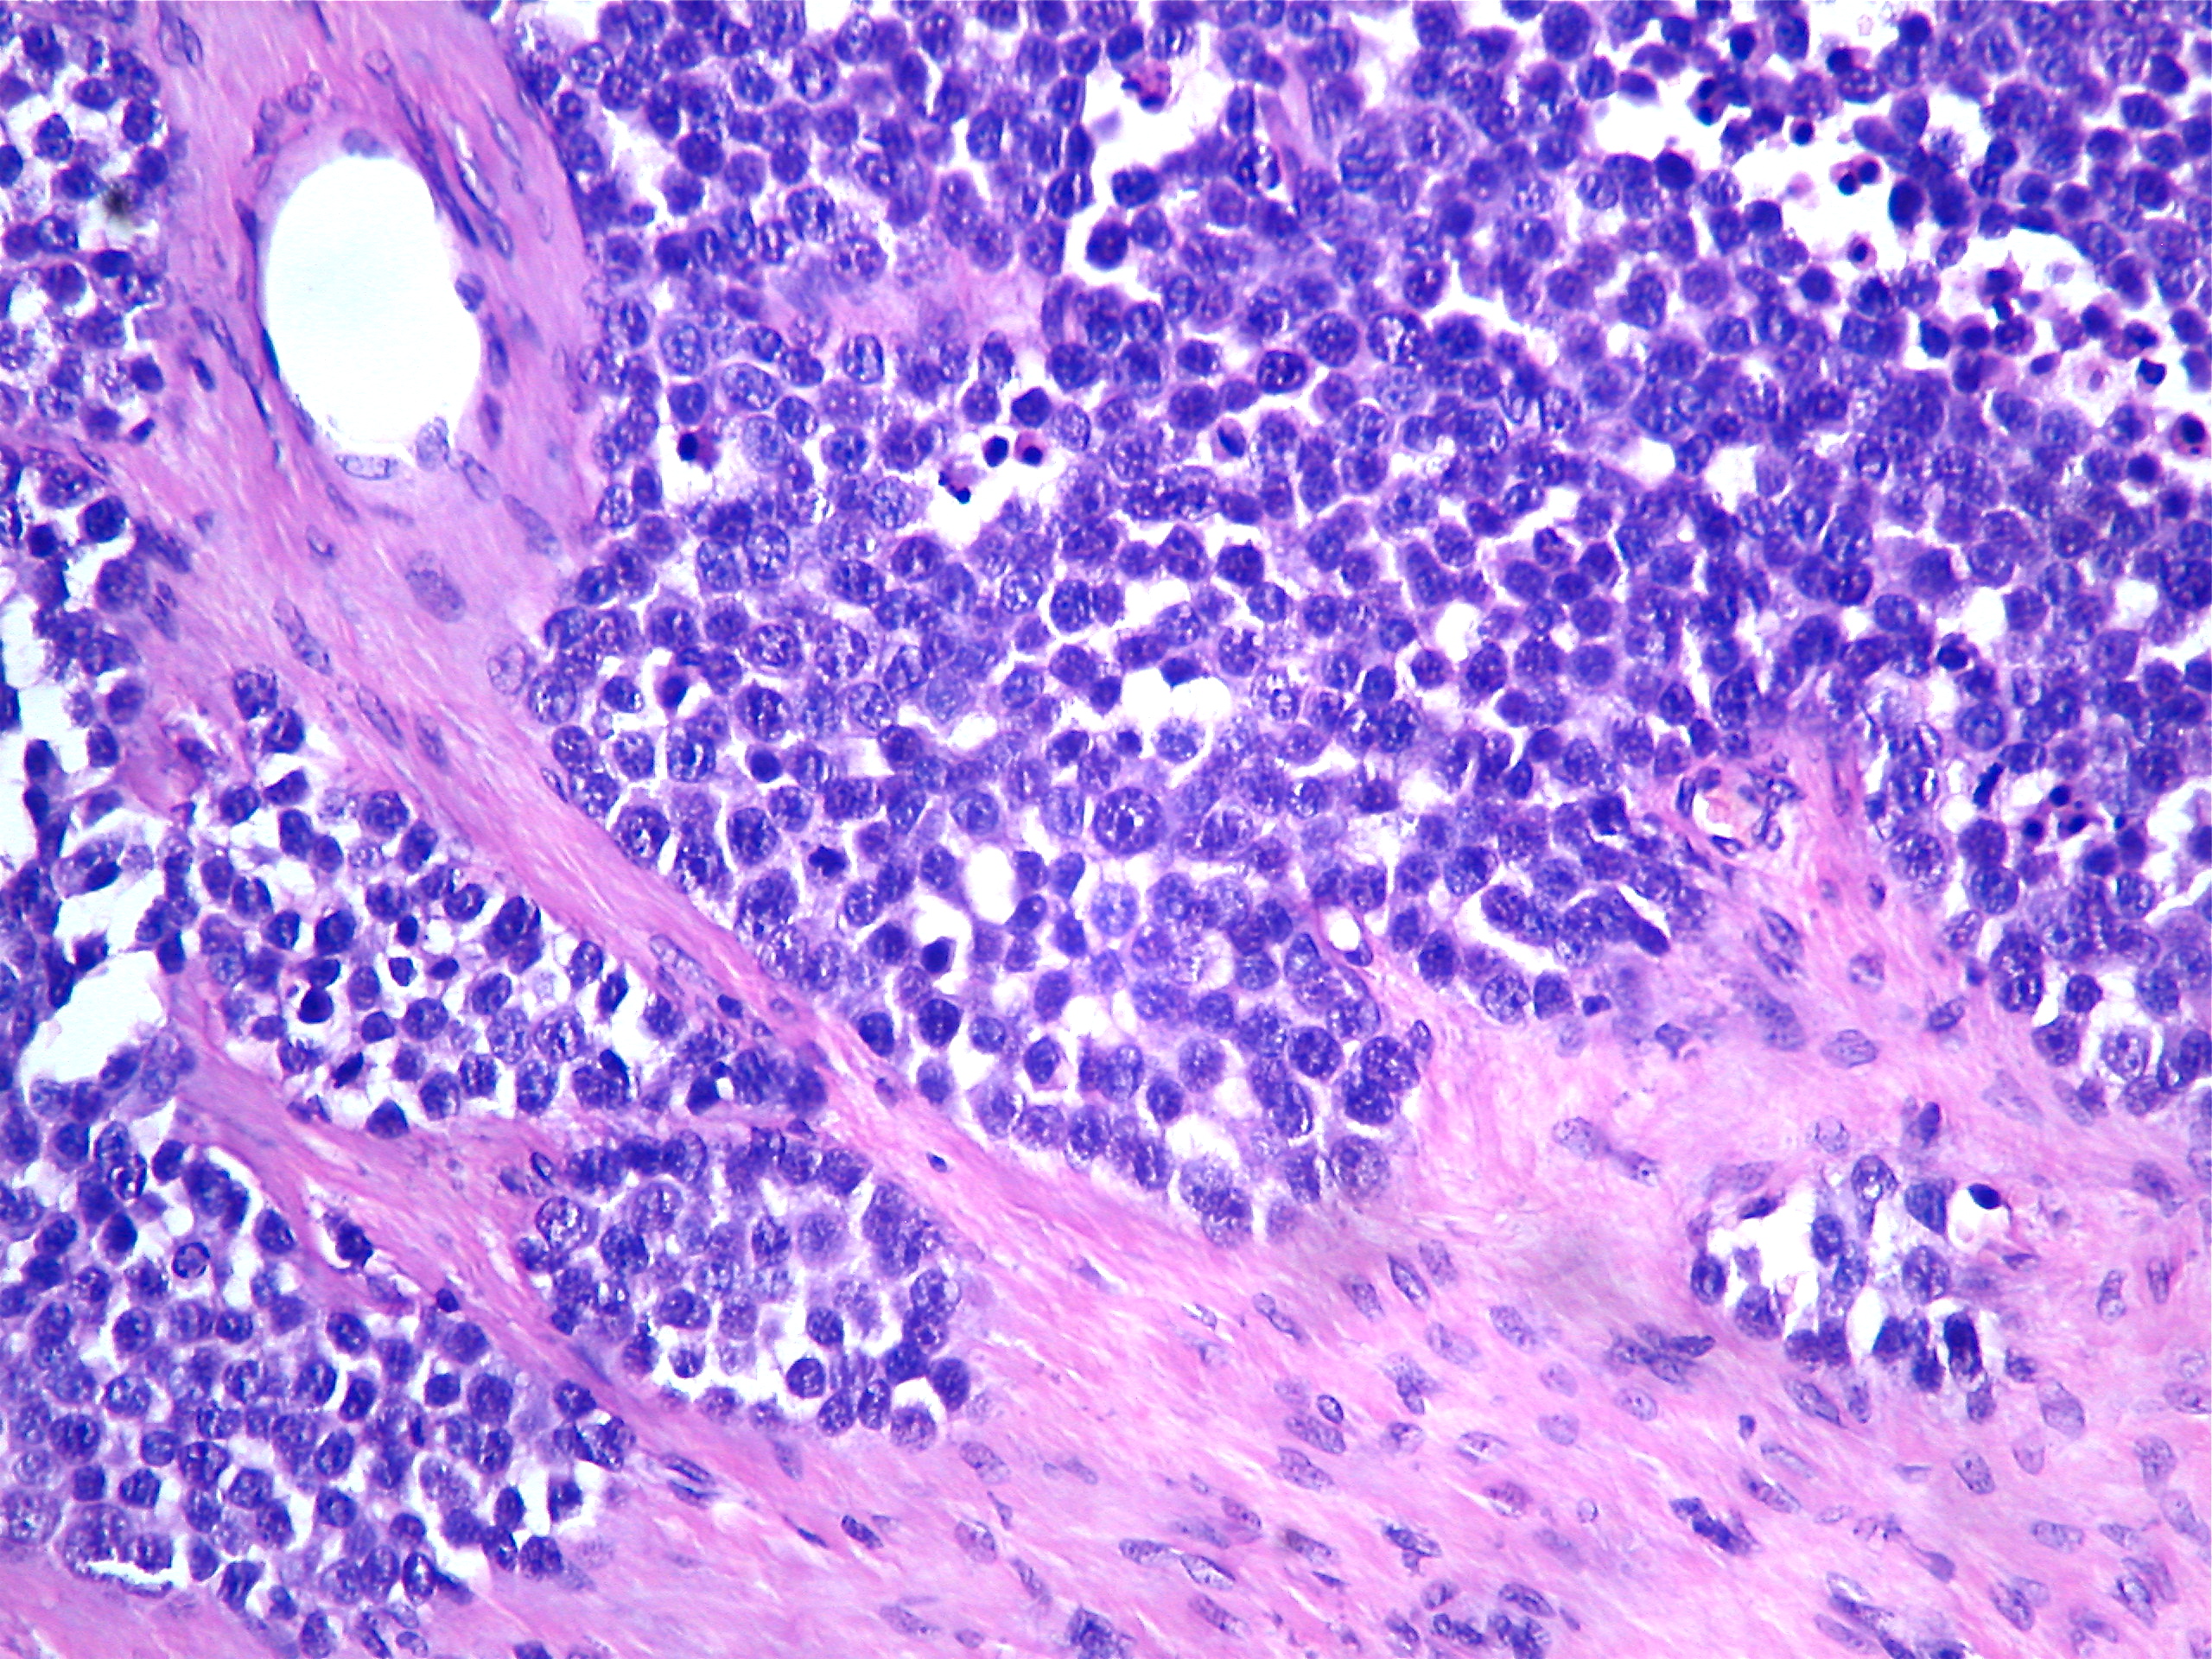

Гистологические изображения фолликулярной кисты яичника